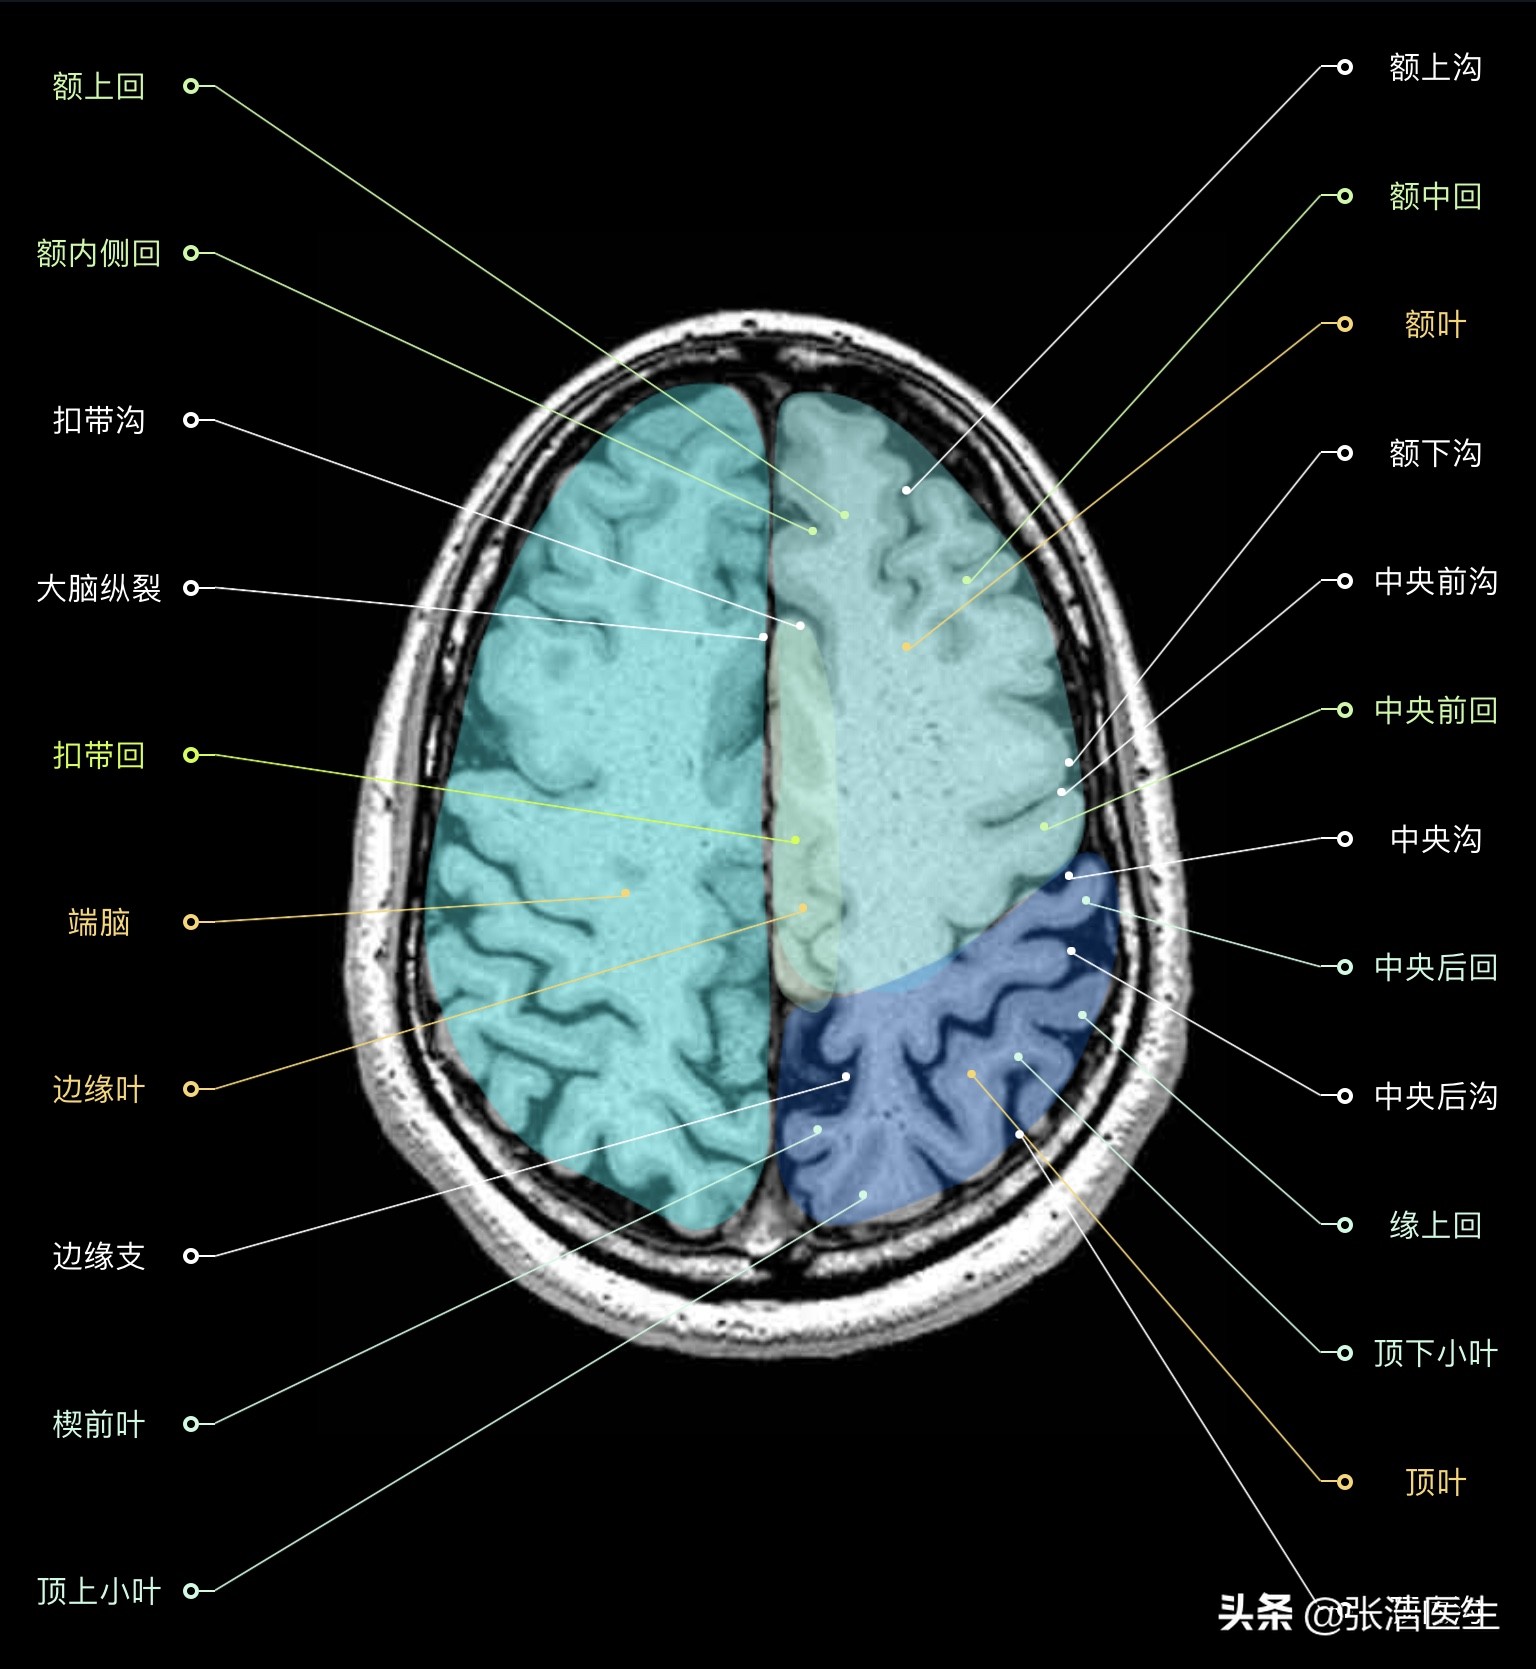

颅脑MRI横断面高清解剖图谱(图层2)